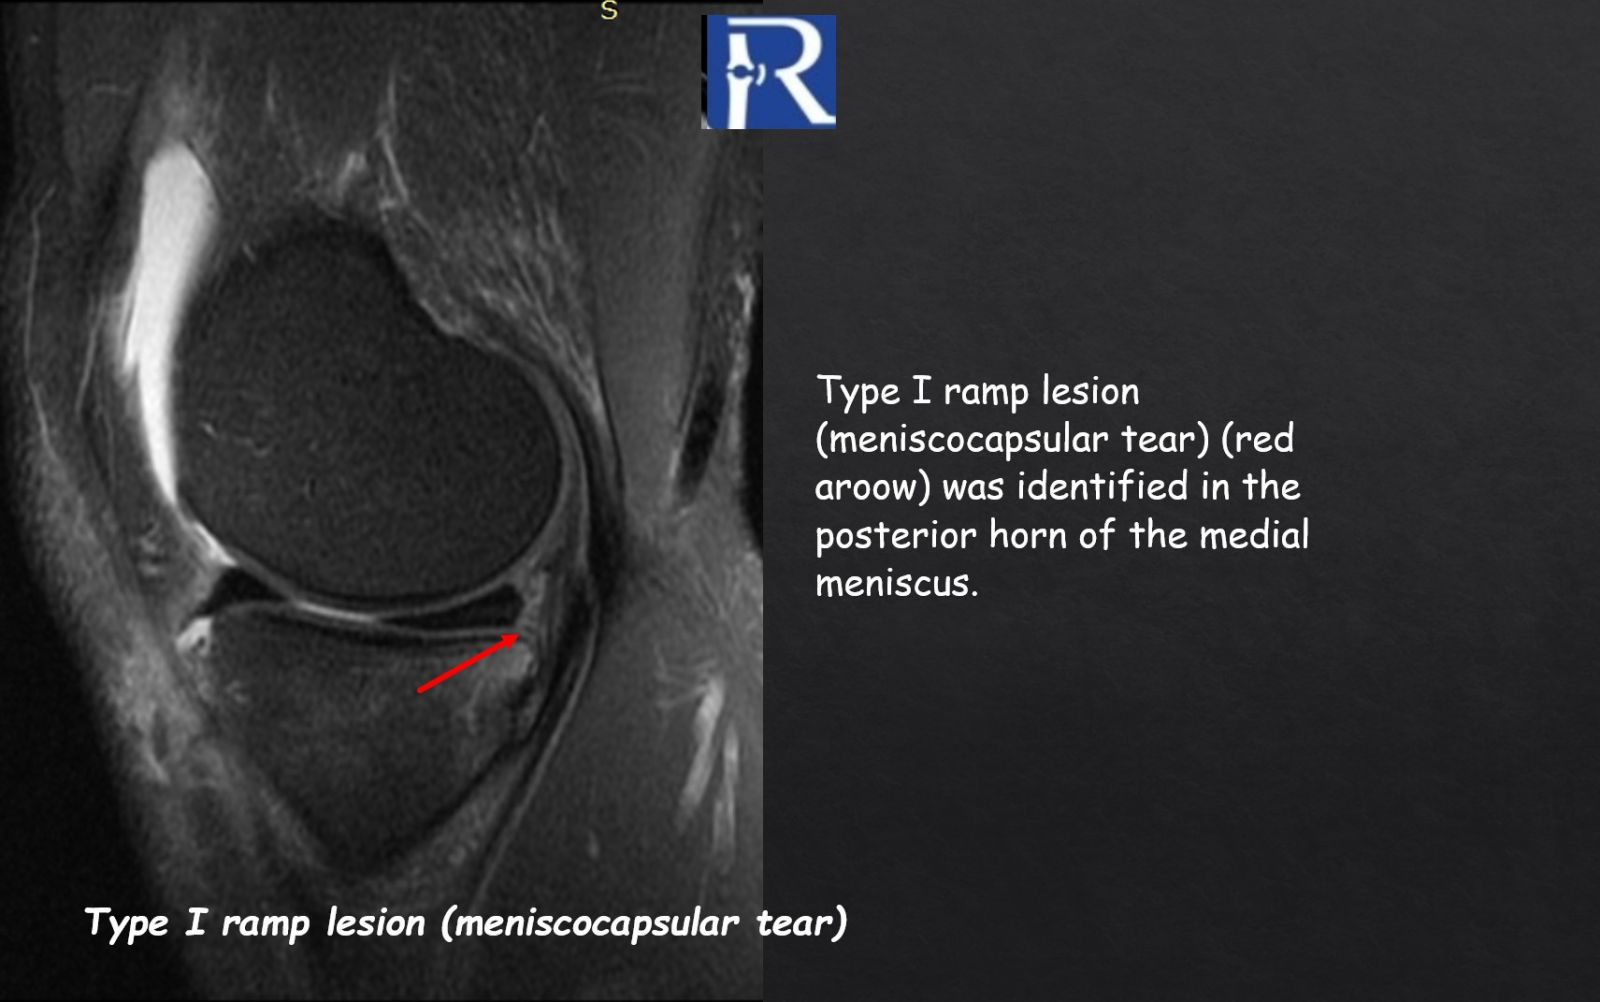

- Medial meniscus Type I ramp lesion